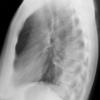

Case 3 RM & UL pneum Lat

Date: 07/04/2004

Views: 7242